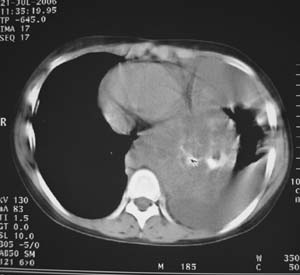

女性,17岁,一年前因股骨病变截肢,现胸憋。

左肺巨大肿块,内散在斑点状高密度骨化影,右肺见多发结节灶,双侧胸膜局限性增厚。有骨肉瘤病史,支持骨肉瘤手术后转移。